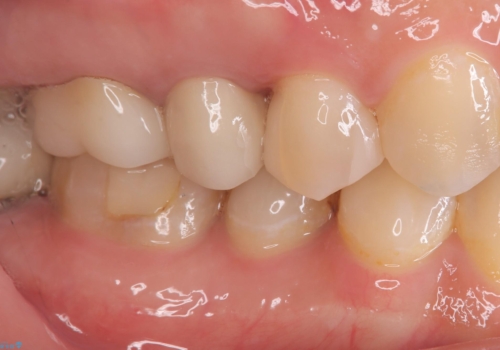

適合不良により汚れが溜りやすく歯肉が腫れている状態だったため、審美性を考慮しセラミックインレーでのやり替えとなりました。

現在入っているインレー・CR裏層を除去し、再度CR裏層・セラミックインレー形成しました。